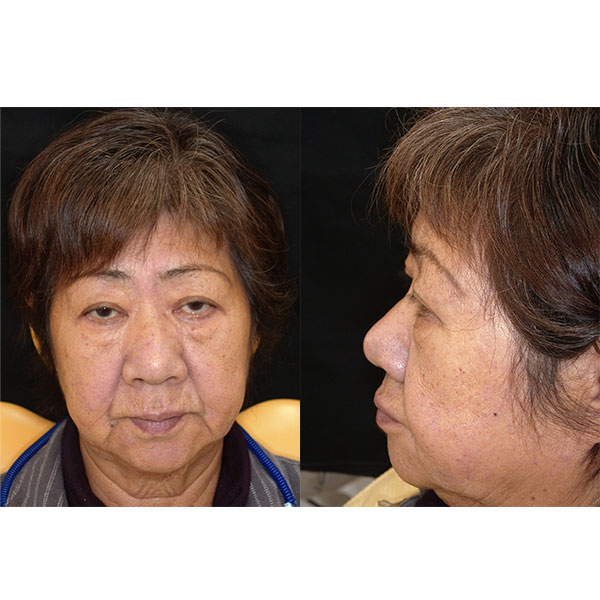

Après la mise en moufle et l'ébouillantage, les dents ont été repositionnées, conditionnées et des caractérisations blanchâtres, pourpres, orange clair, bleues et roses ont d'abord été réalisées au niveau du le bouclier labial. La base a ensuite été incrustée de résines pour prothèses de couleurs orange-rouge, rouge foncé, rouge clair, rose et rose foncé, et tous les polymères à chaud ont été pressés en une seule fois. Après le stockage sous pression, les prothèses finies ont été démouflées, finies et polies. La stratification anatomique tridimensionnelle de VITAPAN EXCELL en masse d'émail, de collet et de dentine avait un aspect absolument naturel dans l'anatomie muco-gingivale reproduite de la base prothétique. Le patient a pu s'habituer rapidement à sa nouvelle prothèse, notamment grâce à l'effet esthétique réussi. Après une courte phase d'adaptation et des corrections minimes dans l'environnement biodynamique, il s'est très bien débrouillé avec sa première restauration prothétique amovible complète et en était pleinement satisfait.